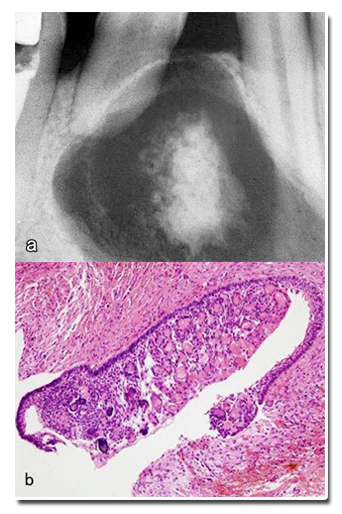

一种囊性的牙源性良性肿瘤,含类似于成釉细胞瘤的上皮成分和影细胞,后者可发生钙化。

病变呈囊性,衬里上皮的基底细胞呈立方状或柱状,胞核远离基底膜;其浅层由排列疏松的星形细胞构成,类似于星网状层;衬里上皮和纤维囊壁内可见数量不等的影细胞灶,并有不同程度的钙化;邻近上皮基底层下方可见带状发育不良牙本质;有的见有广泛牙硬组织形成,类似于牙瘤。

10~19岁,好发部位上颌前磨牙区,病变多较为局限,有时也可发生于颌骨外的软组织。X线表现为界限清楚的放射透光区,单房或多房,有时可伴有牙瘤发生。